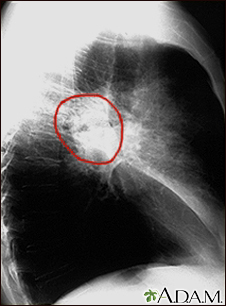

Lung cancer - lateral chest x-ray